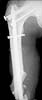

A 23 y.o. male after a car accident transferred to us from elsewhere at 4th day since the injury. He has the pelvic ring lesion including fracture of the left acetabulum, and ipsilateral femoral neck and shaft fractures - images attached. The shaft fracture is open grade II, debrided at the initial hospital - no sign of infection to date.

OK, we just fixed all fractures as the patient shows no infection signs. Posterior column was perQ (nice abbreviation) fixed by a screw and a wire, rami - by screws. Then closed locked nailing was performed (i placed a single screw at the upper level - is it commonly acceptable?) and "miss a nail" three cancellous screws to the neck (at the moment we have no more available implants suitable for this lesion like gamma nail etc, so the choice was easy :-). The external fixator left in place as a "local sceletal traction" for a couple of weeks. Acetabular, femoral shaft and neck images attached.